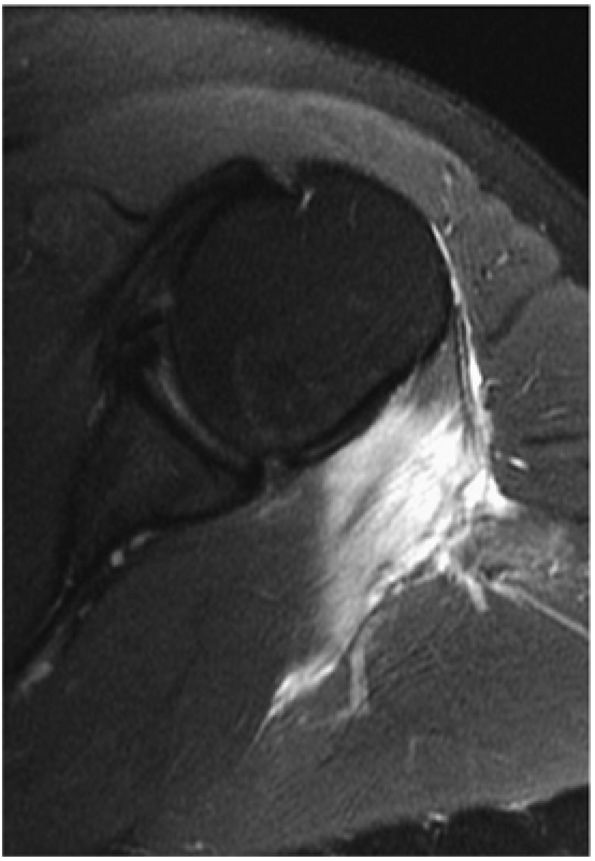

FIGURE 8.102 ● (A) The anterior undersurface of the acromion and the coracoacromial ligament form the coracoacromial arch. The subacromial subdeltoid bursa facilitates the passage of the rotator cuff and proximal humerus under the coracoacromial arch. (B) A superior axial image shows the anterior-to-posterior extent of the coracoacromial (CA) ligament perpendicular to the supraspinatus tendon. The fluid in the subacromial-subdeltoid bursa represents fluid between two serosal surfaces in contact with each other. One serosal surface is contributed by the undersurface of the coracoacromial arch and deltoid, and the other serosal surface is on the bursal side of the cuff.

|

![]() |